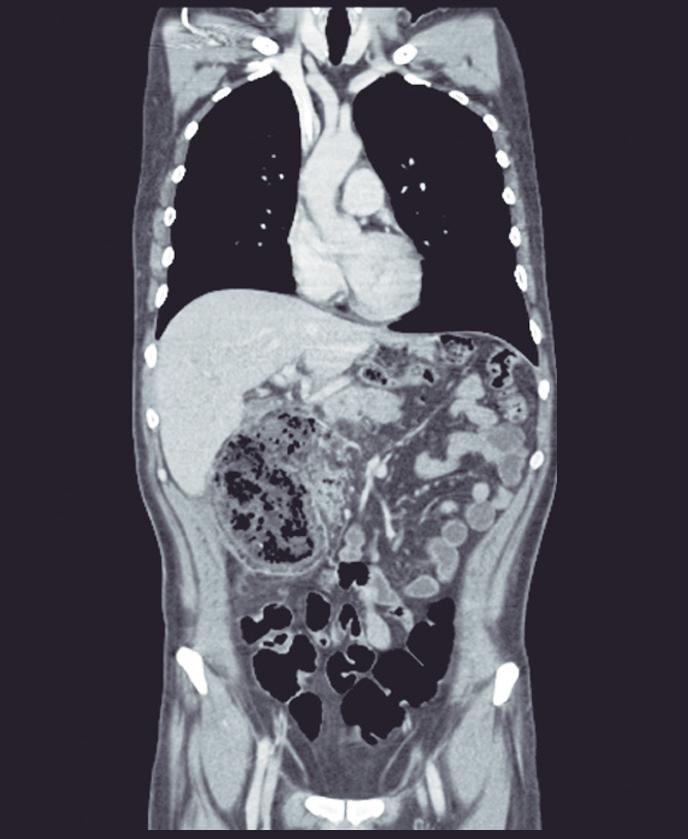

Evaluación endoscópica e histológica

La endoscopía superior es un procedimiento fundamental para el diagnóstico, la evaluación de la respuesta al tratamiento y el monitoreo a largo plazo de la actividad de la EEo. Los hallazgos endoscópicos típicos incluyen edema (reducción de vascularidad), anillos esofágicos fijos, exudados blancos, surcos longitudinales, estenosis, estrechamiento de la luz esofágica, friabilidad de la mucosa (mucosa en papel crepé) y una consistencia firme de la mucosa al realizar biopsias (signo de “tracción" o "resistencia”) en pacientes con fibrosis (Figura 1). Estos hallazgos no son patognomónicos y no constituyen un criterio diagnóstico; sin embargo, cuando se evalúa de forma cuidadosa, en la gran mayoría de los casos se pueden observar.19-21

Es imperativo llevar a cabo una exploración endoscópica minuciosa en todos los casos de sospecha de patología esofágica. En el contexto de la EEo, esto requiere dedicar un tiempo adecuado a la visualización completa del esófago tras la intubación, evitando desplazar o raspar los exudados, insuflando adecuadamente el esófago, eliminando cuidadosamente mucosidad, saliva o detritus, y evaluando el calibre esofágico. Esta evaluación puede incluir la retroflexión en la unión gastroesofágica para estimar el diámetro de las estenosis en dicha región.22

Un elemento fundamental en la evaluación de la EEo es la aplicación del puntaje de referencia endoscópica para la esofagitis eosinofiílica (EREFS por sus siglas en inglés: Eosinophilic Esophagitis Endoscopic Reference Score).20 El acrónimo EREFS también refleja las cinco características endoscópicas principales de la EEo: Edema, anillos esofágicos (Rings), Exudados, surcos longitudinales (Furrows) y estenosis (Stricture). Estas características se clasifican según su severidad mediante un sistema de puntuación que oscila entre 0 y 9, considerándose la región esofágica con la alteración más marcada. El EREFS cuenta con validación interna y externa, y ha demostrado una elevada capacidad para diferenciar la EEo de otras patologías no relacionadas en poblaciones pediátricas y adultas, además de correlacionarse con la respuesta terapéutica.23-25 Por estos motivos, el EREFS constituye un sistema estandarizado para la evaluación

En el panel A se observa un esófago con edema difuso y pliegues longitudinales; en el panel B se aprecia edema con pliegues y exudados blanquecinos; en el panel C se evidencia un estrechamiento luminal acompañado de anillos esofágicos y exudados; y en el panel D se muestra un desgarro mucoso posterior a la dilatación con bujía de Savary, hallazgo esperado tras este procedimiento terapéutico.

Figura 1. Características endoscópicas de la esofagitis eosinofílica